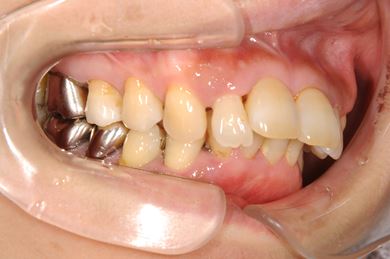

部分矯正治療+骨再生インプラント治療

| 性別/年齢 | 女性 / 52歳 | ||||||||||||||||||||||||||||||||

| 主訴 | 上前歯の歯並びが気になる | ||||||||||||||||||||||||||||||||

| 治療方針 | 全体的に骨が薄く、なるべく歯に負担を立てない治療計画にしました。口元も下げたいため、歯を少し細く削り後ろにさげました。部分矯正後、下顎のインプラントも併用しています。 | ||||||||||||||||||||||||||||||||

| 治療内容 | 部分矯正(唇側矯正ホワイト)、インプラント2本(GBR)、メタルボンドセラミッククラウン3本 | ||||||||||||||||||||||||||||||||